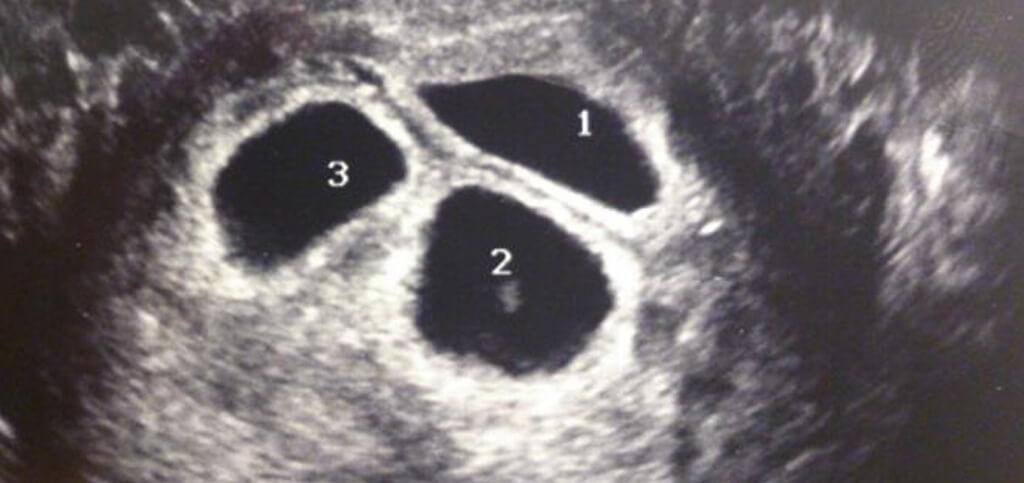

Sarah and Andy Justice were thrilled upon hearing the news they were chosen by a third birth mom. They were so thrilled, in fact, that they were there for her every step of the way. The birth mother even invited them to an ultrasound appointment.

At the ultrasound appointment, Sarah and Andy would have a chance to see their new child for the first time. However, something strange showed up on the scan that displayed on the ultrasound monitor. Everything looked normal for the birth mom, but to her surprise and everyone else's, she was actually carrying three babies instead of one!

Sarah, Andy, and their birth mother were completely shocked to see three heartbeats on the ultrasound monitor. They have worked so hard for so long just to be blessed with one bundle of joy, but now the universe was giving them three.